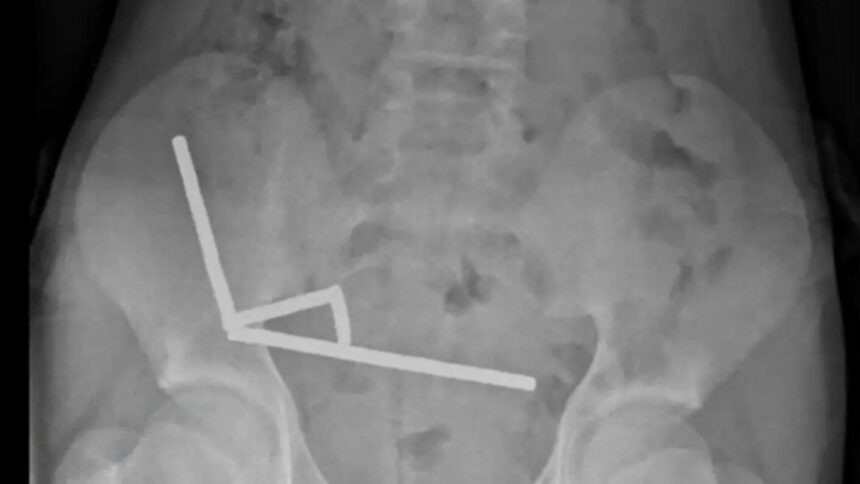

Băiatul a fost internat la Spitalul Tauranga, pe Insula de Nord, după ce a acuzat dureri abdominale intense timp de patru zile. În timpul consultației, el le-a spus medicilor că înghițise între 80 și 100 de magneți mici, însă intervenția chirurgicală a relevat o realitate mult mai gravă: aproape 200 de magneți se aflau în intestinul său. Imaginile radiologice au arătat patru lanțuri magnetice prinse în diferite zone ale intestinului, provocând blocaje în circulația sângelui și necroză intestinală, o complicație care i-a pus viața în pericol. Medicii au fost nevoiți să îndepărteze o porțiune din intestin pentru a salva pacientul.